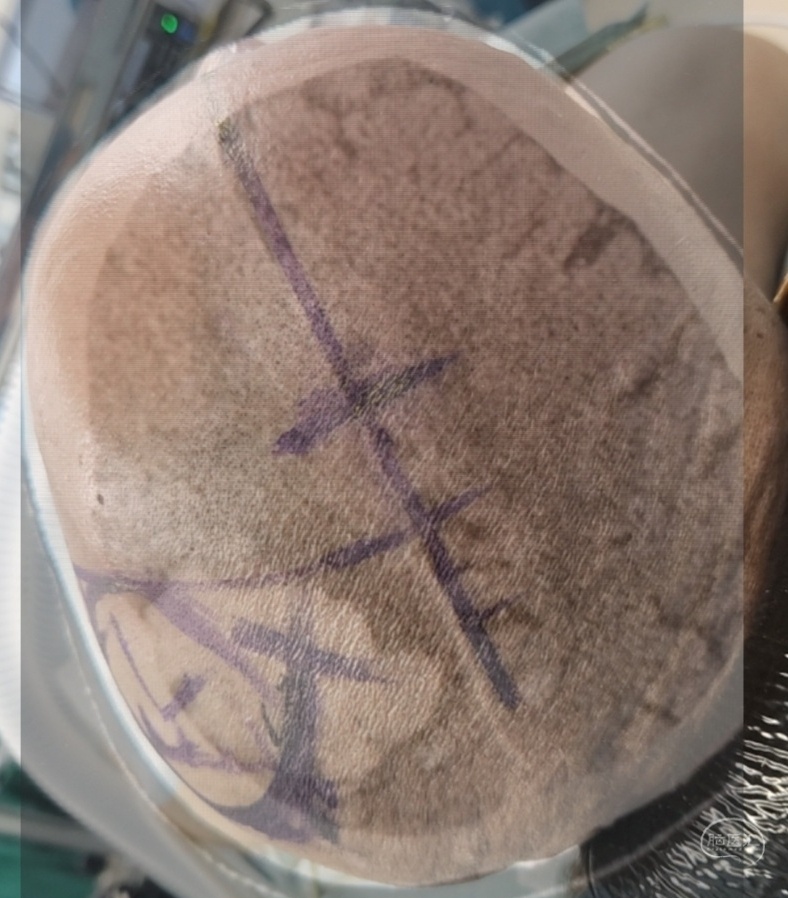

根据术前重建大致定位血肿上下界,再以前囟点后5cm(中央沟上端点)和耳前凹陷上5cm(中侧裂点)定位中央沟体表投影,即为血肿前界,以血肿为中心设计一小弧形切口

术中证实定位准确,刀碰皮至关颅最后一针100分钟。